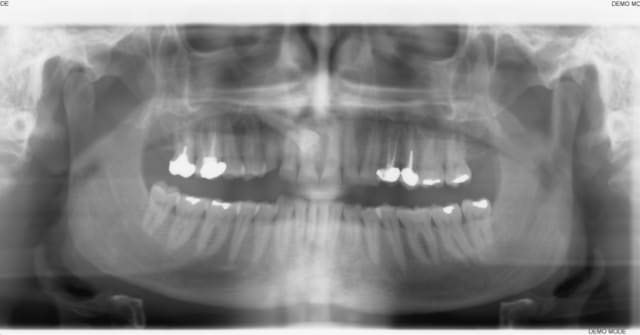

ce patient, 40 ans, non fumeur, sans de pb de santé particulier consulte pour un problème esthétique sur la 53. il est aussi inquiété par l'usure de ses incisives.

l'abrasion des incisives, l'éggression des groupes incisivo-canin maxillaire et mandibulaire pour compenser cette abrasion, et l'occlusion me laissent dubitatif.

J'avais envisagé dans un premier temps de proposer de l'ortho pour lever la supracclusion et permettre la pose d'un implant pour remplacer la 13, et reconstituer les incisives, mais l'absence d'une veritable perte de DV me laisse un peu sec pour le plan de traitement. Toutes les idées sont les bienvenues.

Reste à virer la canine incluse, puis lacteale et poser ton implant avec MCI ?

A bien y regarder, 16 et 17 sont obturées et doivent être couronnées, les coiffes sur 24-25 sont à refaire, reste 14-15-26-27 qui pourront être reconstituée à l'aide d'inlay. Je pense que je vais m'orienter vers le plan de traitement sans ortho.